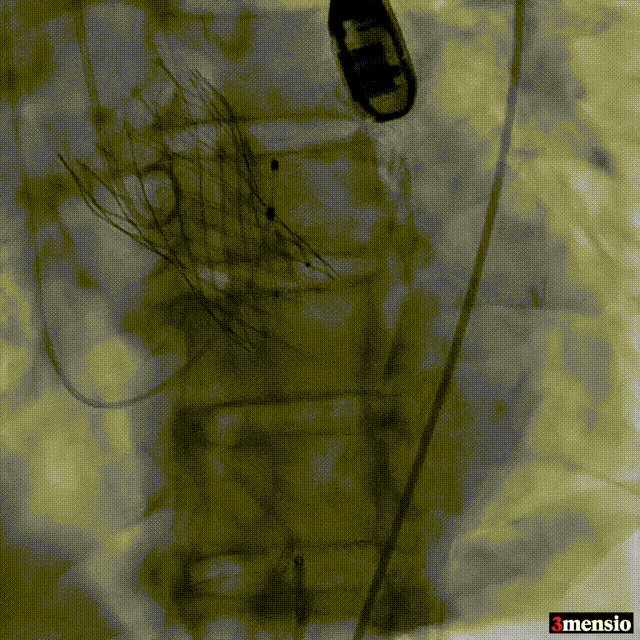

根部造影

跨瓣

20mm球囊预扩